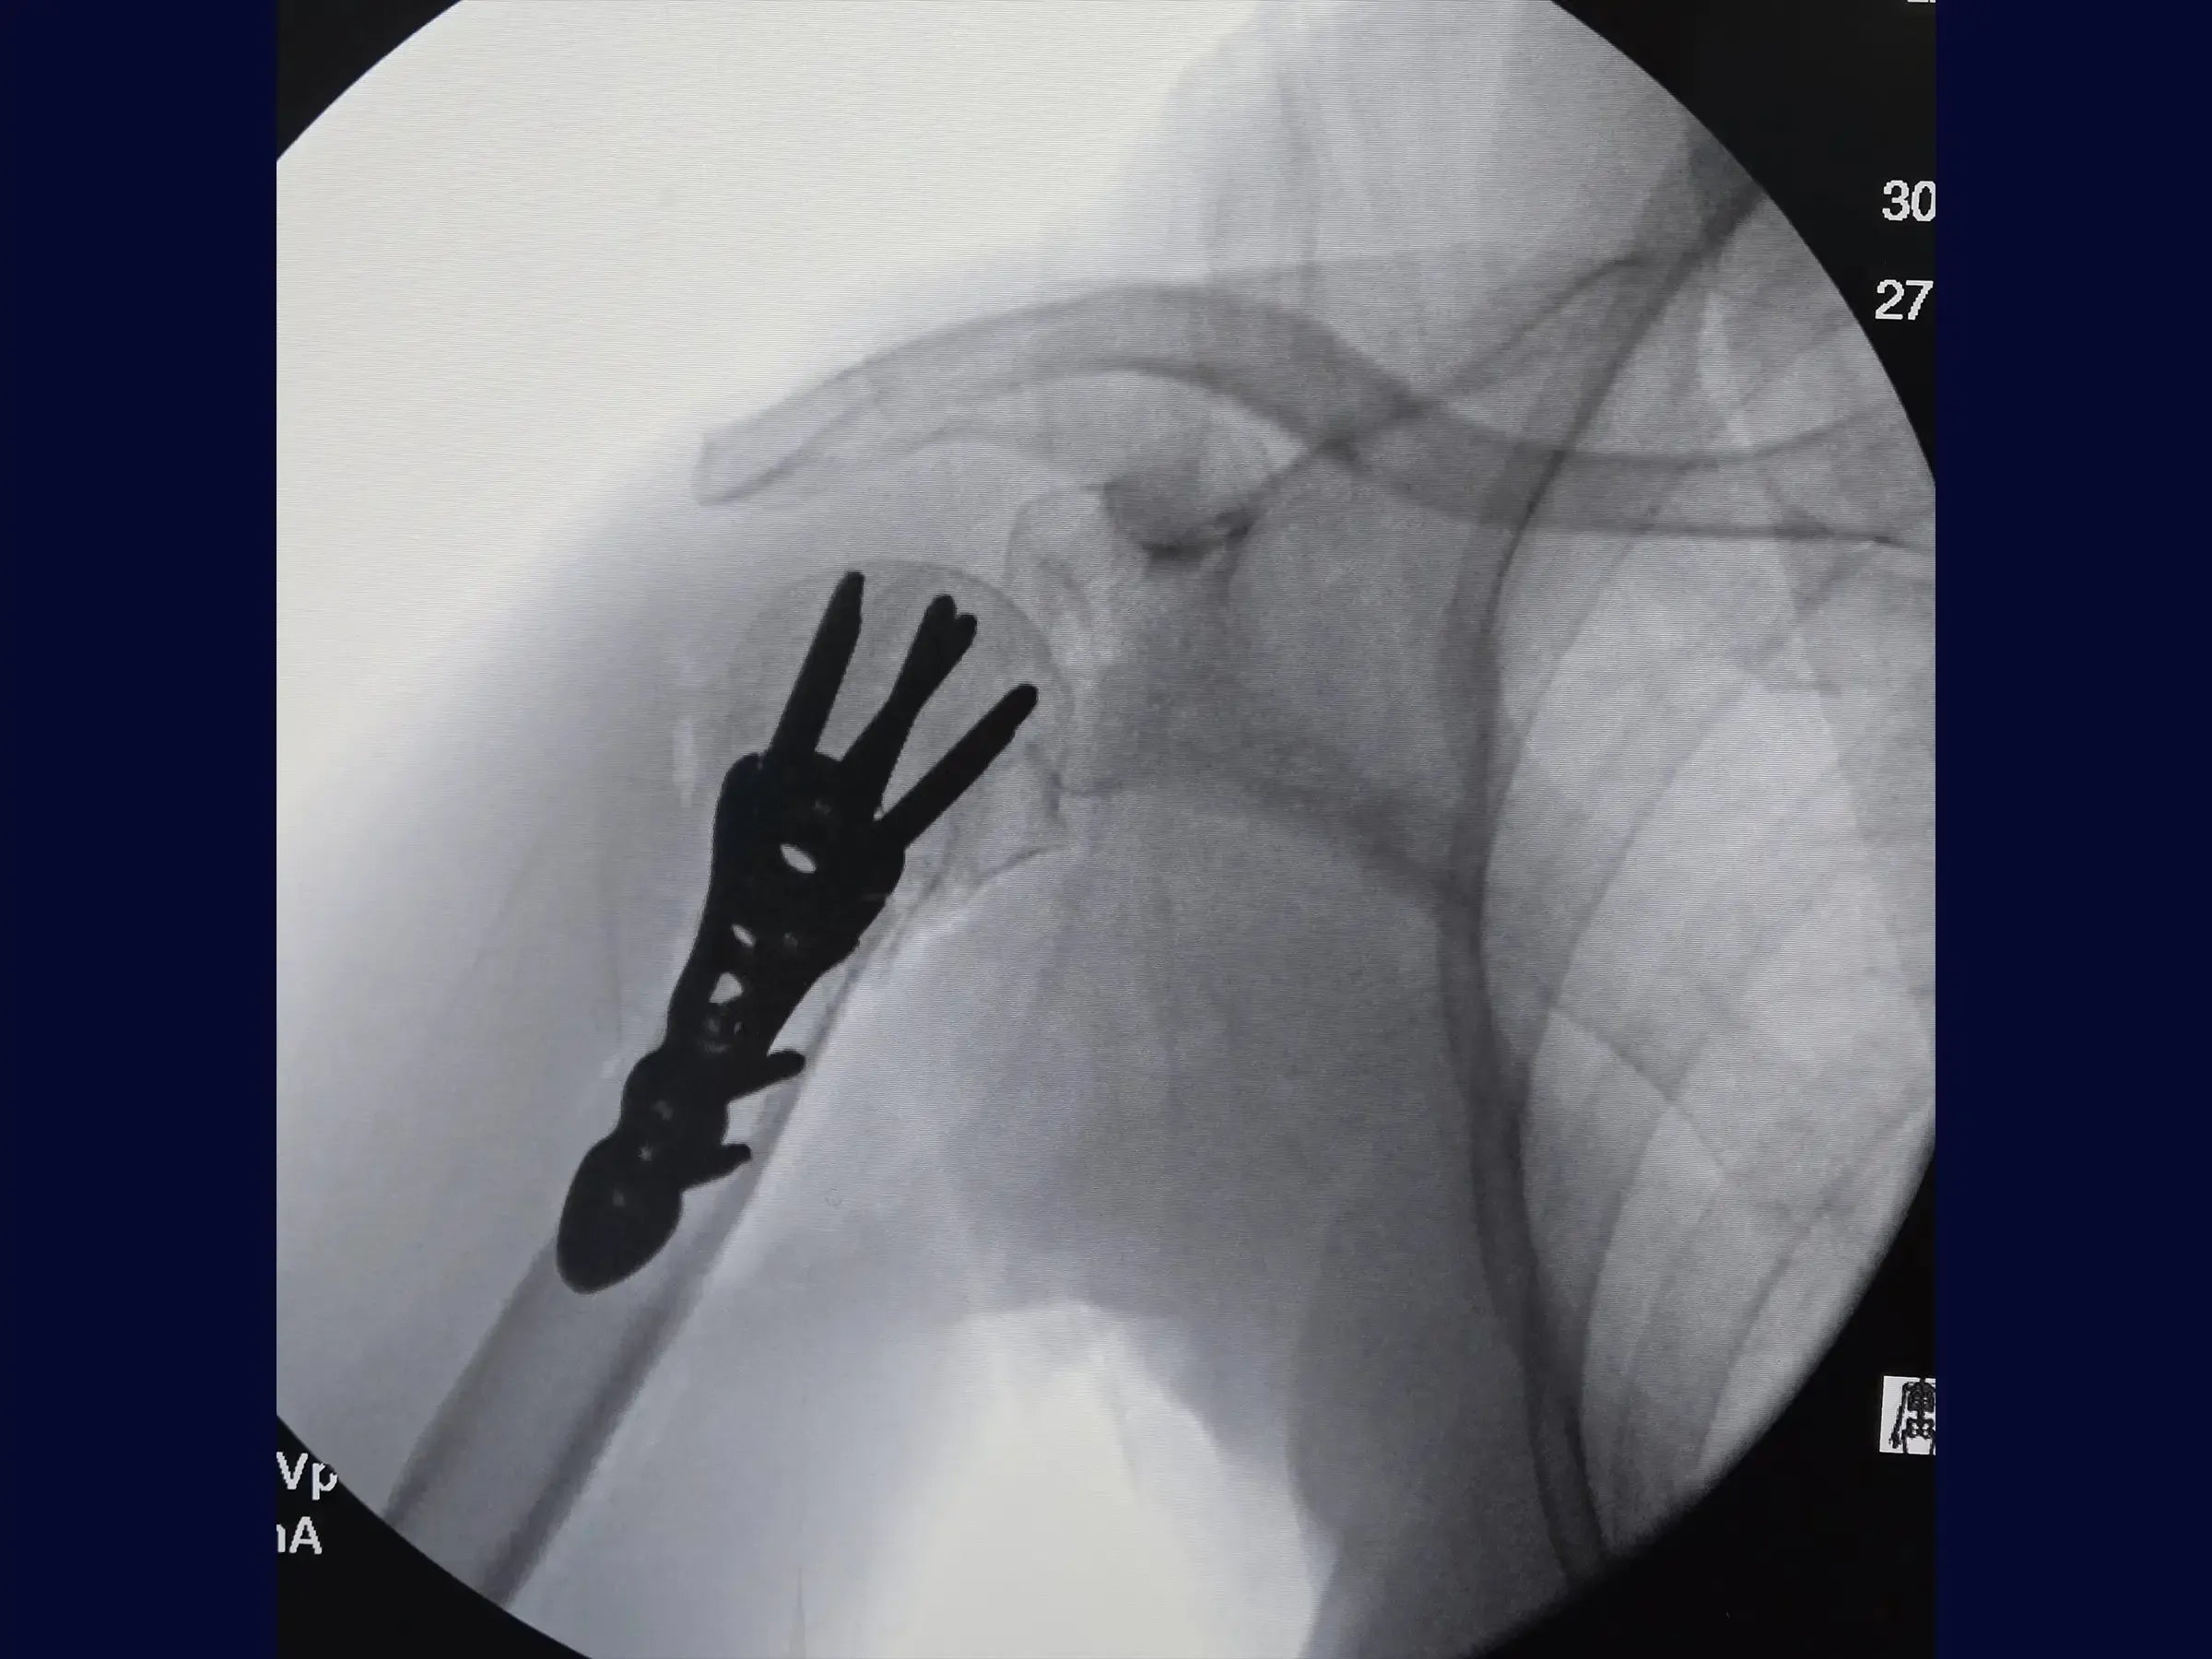

Proximal Humerus Fracture in 2 Parts (Deltopectoral Approach)

Master the treatment of proximal humerus fractures in 2 parts. This training offers a technical immersion in the deltopectoral approach for osteosynthesis, presented in 4K video from the surgeon's perspective, detailing each step of the procedure to optimize results.

- Anatomical reduction of proximal humerus fractures and provisional fixation.

- Manoeuvres for valgization of the humeral head.

- Brocage technique and measurement of screws for definitive subchondral fixation.

- Secure Subchondral Fixation: Drilling methodology with sensitivity for precise positioning of screws in the subchondral bone, without perforating the cartilage, with initial insertion of the screws from the calcaneus.